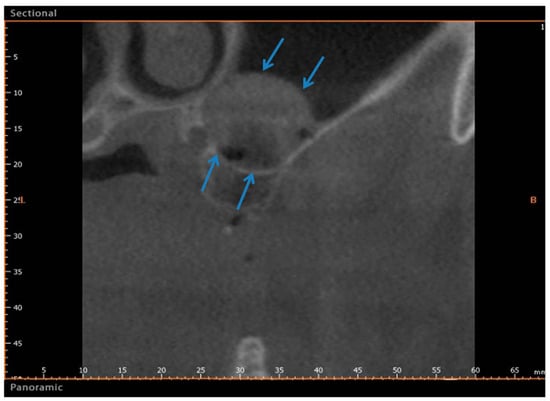

2.1. Group I

2.2. Group II

4. Materials and Methods